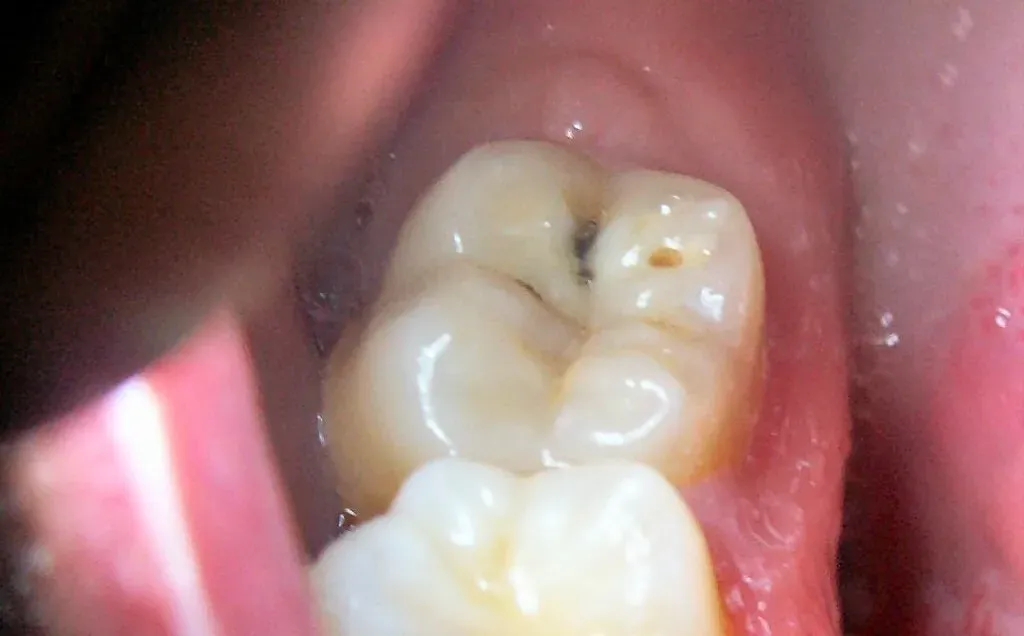

Trước khi tìm hiểu răng sâu nhẹ có nên trám không thì cần biết sâu răng nhẹ là gì. Sâu răng nhẹ là giai đoạn đầu của quá trình tổn thương mô cứng của răng do vi khuẩn trong mảng bám gây ra. Lúc này môi trường khoang miệng không được vệ sinh đúng cách. Khi đó vi khuẩn sẽ sản sinh axit, làm mất khoáng men răng. Từ đó dần dần hình thành các lỗ nhỏ li ti trên bề mặt răng. Nếu không được phát hiện và điều trị kịp thời, sâu răng có thể tiến triển nghiêm trọng hơn. Nó sẽ ảnh hưởng cấu trúc răng và sức khỏe răng miệng tổng thể.

- Ban đầu, sâu răng thường biểu hiện dưới dạng đốm trắng hoặc nâu nhỏ trên bề mặt răng. Đặc biệt là ở rãnh nhai hoặc kẽ răng.

- Theo thời gian, những đốm này có thể phát triển thành các lỗ nhỏ do men răng bị phá hủy